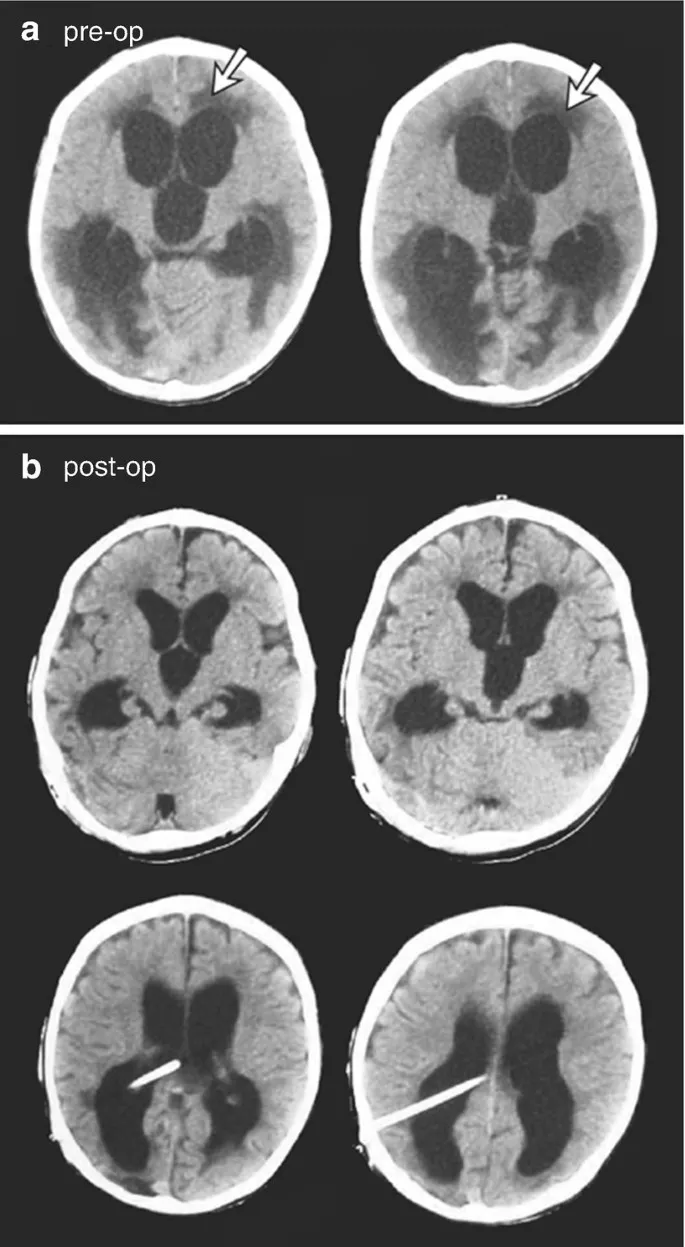

Raised ICP & Hydrocephalus - Pressure Cooker Brain

- Raised ICP: Symptoms: Headache, vomiting, papilledema. Late: Cushing's triad. CT findings: Effaced sulci, compressed ventricles/cisterns.

- Hydrocephalus: ↑CSF volume causing ventricular dilatation (Evan's Index > 0.3).

- Acute sign: Transependymal CSF flow (periventricular lucency on CT / T2 hyperintensity on MRI).

- ⭐

Transependymal CSF seepage (periventricular lucency on CT / T2 hyperintensity on MRI) indicates acute/uncompensated hydrocephalus.